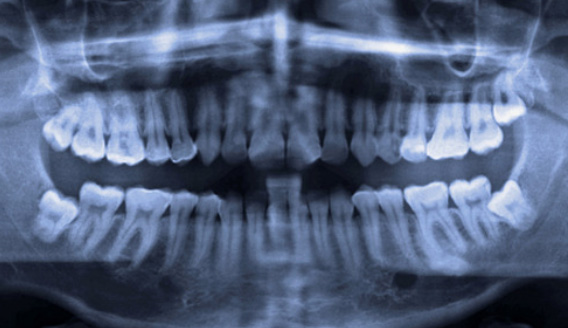

사랑니는 우리 입속에 가장 뒤에 난 어금니를 말하며, 전문용어로 설명해 드리면 제3대구치라고 하며 얼굴을 중심으로 좌우로 8번째 자리하고 있는 치아를 말합니다. 사랑니는 사춘기 이후에 자란다고 합니다. 사춘기에는 여러 가지 감정을 느끼게 되고 그 감정 중 하나가 사랑이라는 감정이지요. 그래서 이 치아를 사랑니라고 부른다고 합니다.